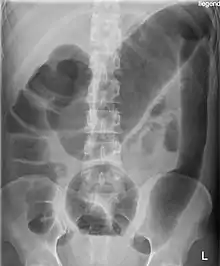

Toxic megacolon in a patient with ulcerative colitis: The patient subsequently underwent a colectomy.

Massively dilated colon with air-fluid level can be seen on abdominal radiograph or CT scan.[5][6]